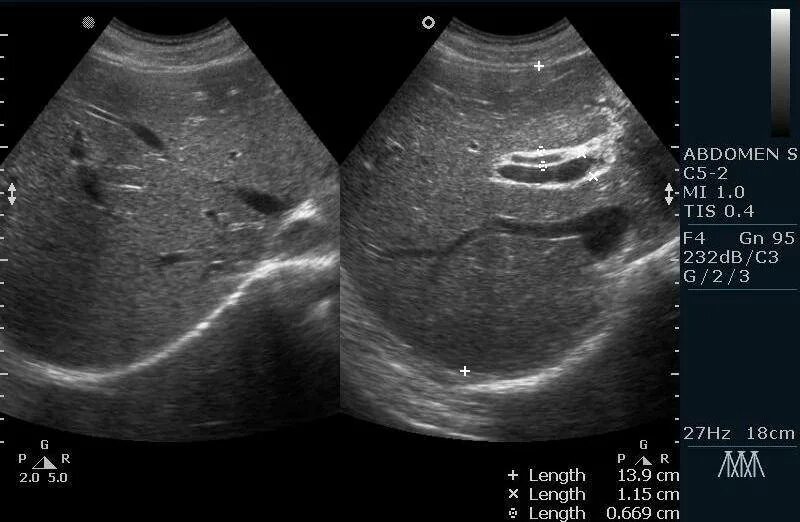

Где лучше сделать узи брюшной полости